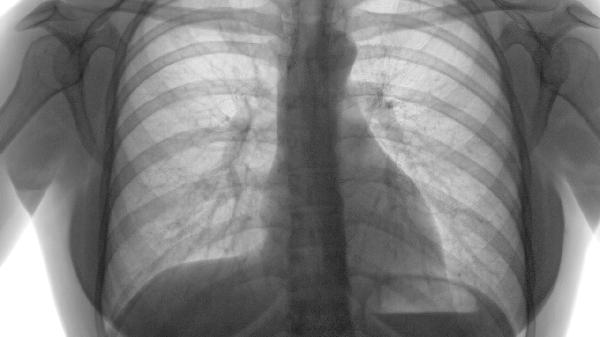

肺气肿患者需保持高蛋白、富含维生素C的饮食以修复肺泡损伤,如鸡蛋、西兰花、柑橘类水果。每日进行30分钟低强度有氧运动如散步、太极可改善肺功能,运动时监测血氧饱和度避免缺氧。居家使用空气净化器减少刺激物吸入,定期做肺功能评估调整治疗方案。突发气促或咳血需立即就医。